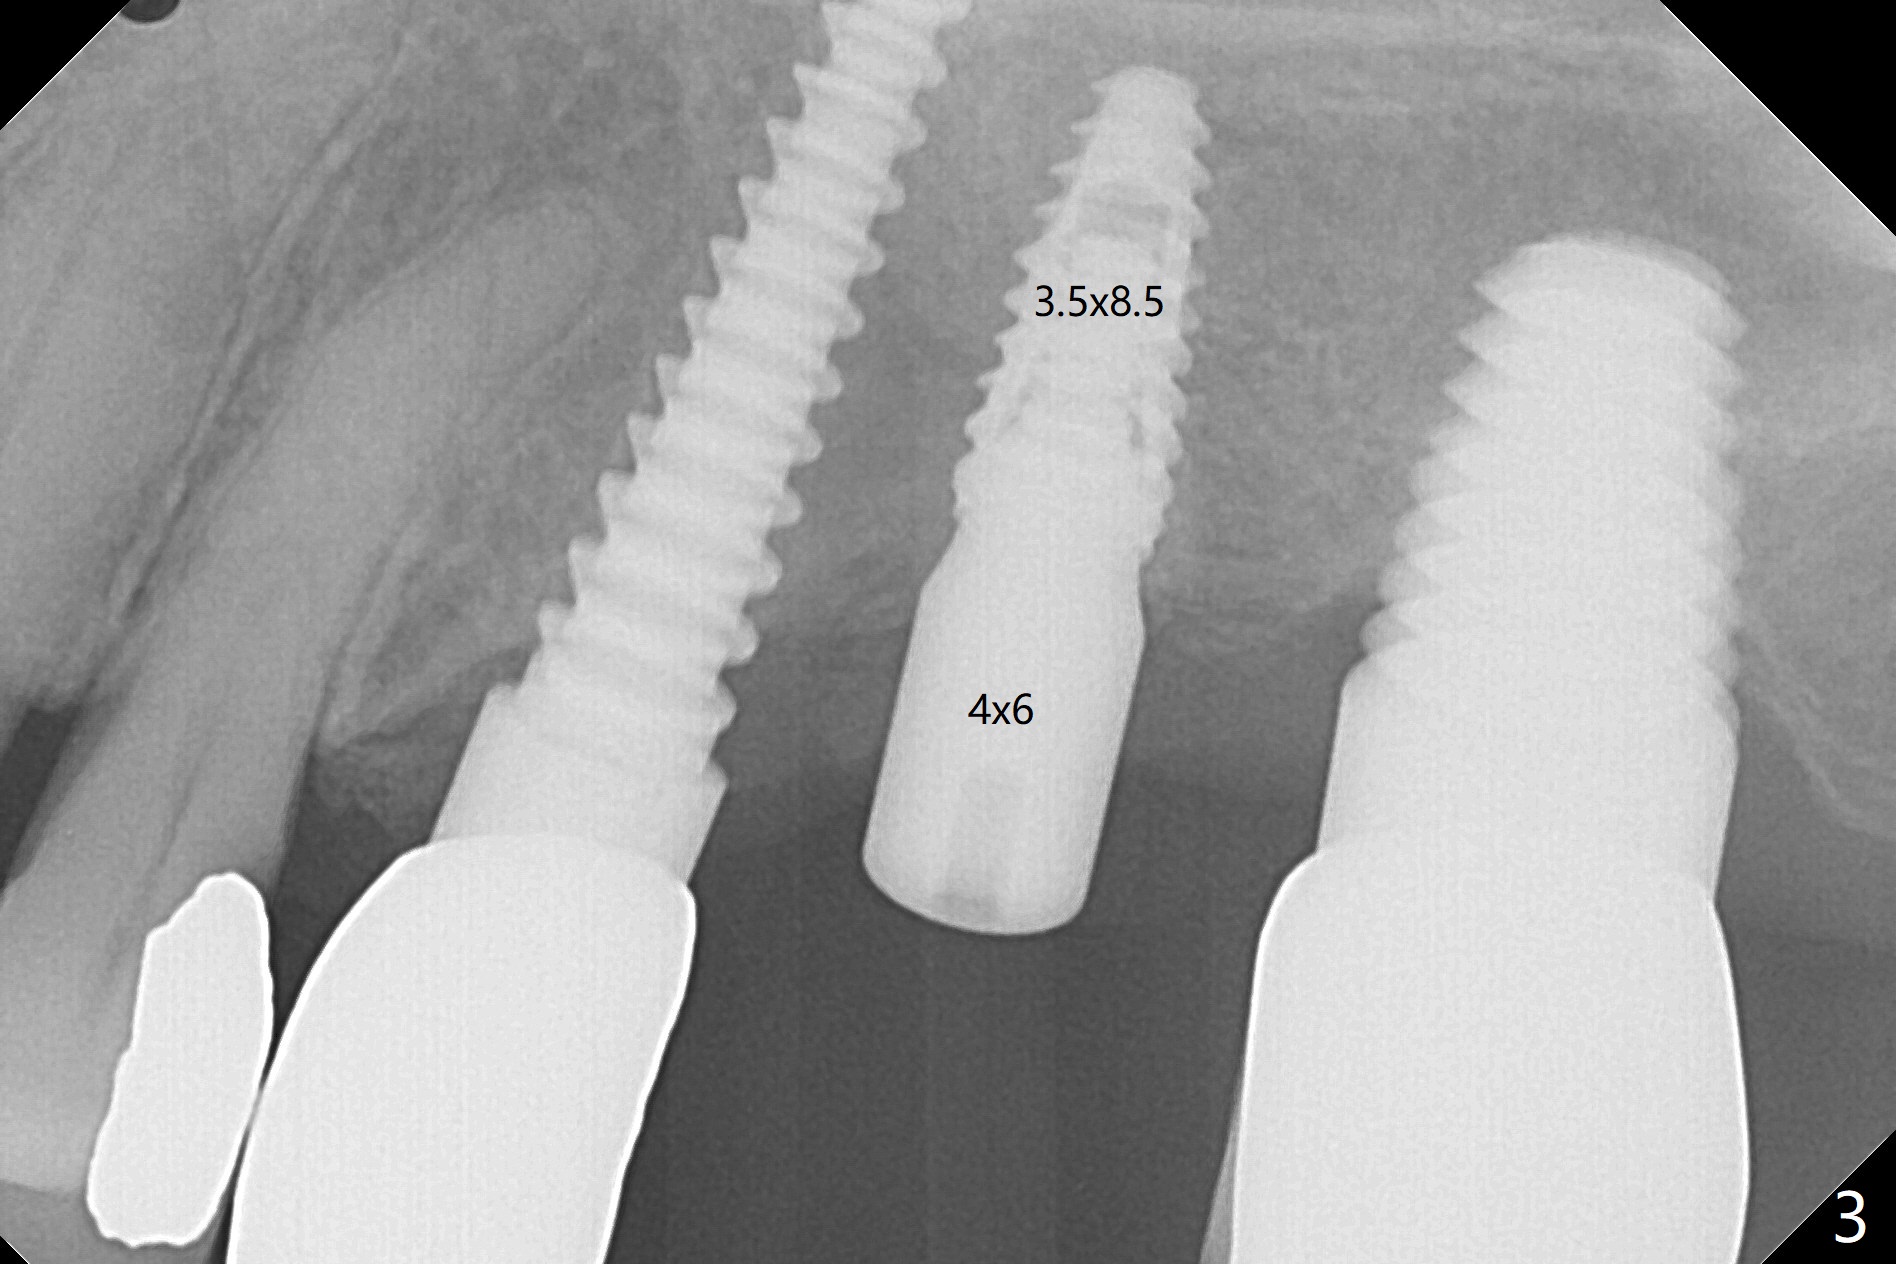

After osteotomy with guide and 2.2 mm drill for ~ 4 mm at #14, a bone expander (1.3/2.3 mm) is used free hand for sinus lift for 12 mm (from the gingival margin, Fig.1; a 10 mm long implant is planned). Following the next expander (1.7/3.1 mm) for the same depth with binding, the sinus membrane is suspected to have perforated. A piece of Osteogen Plug is inserted into the osteotomy as deep as possible with the purpose to repair the sinus membrane (no bone graft being used), followed by placing a 3.5x8.5 (instead of 10) mm implant with insertion torque ~ 25 Ncm (Fig.2,7-9, CT). As compared to preop CT (Fig.4-6), the previously grafted bone is lifted into the sinus by the bone expanders and the implant (Fig.7*). At the same time, the grafted bone has been condensed and pushed buccally (B) (Fig.8,9 *). A 4x6 mm healing abutment is inserted (Fig.3). There is crestal bone loss 6 months postop (Fig.10). Buccal plate atrophy involves the 3 implants in a row (Fig.11). The crown is loose 1 year 8 m post cementation (Fig.12). After proximal reduction, the crown/abutment rotates and sits down substantially (Fig.13). Since the crown is extremely long, it cannot be seated together with the abutment. The latter is seated with X-ray confirmation before proximal reduction of the crown (Fig.14).